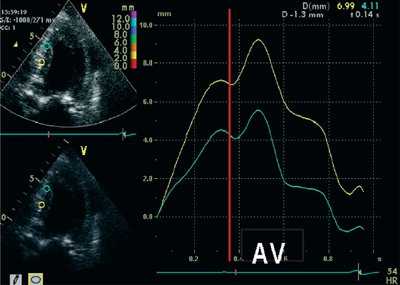

На рис. 1-5 представлены примеры проведения количественного анализа SQ (Strain quantification) тканевого допплеровского изображения в программе Q-lab 3.0. Принцип выделения изоволюмических фаз демонстрируется на рис. 1. Принцип количественного анализа деформации (ε) сегментов миокарда представлен на рис. 2-3, скорости деформации (SR) - на рис. 4, графиков SR/(ε) - на рис. 5.

![Пример определения длительности изоволюмических фаз при постобработке данных тканевого допплеровского исследования у пациента с выраженной ГЛЖ]()

Рис. 1. Пример определения длительности изоволюмических фаз при постобработке данных тканевого допплеровского исследования у пациента с выраженной ГЛЖ.